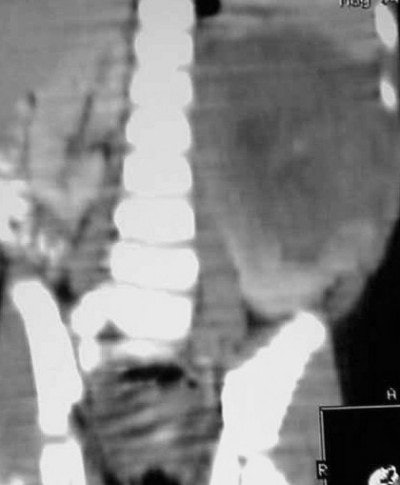

Case 1: The patient is a three-year-old black female who appears to be in no distress. The mother stated that she was giving the child a bath and noticed that her abdomen looked distended, and harder on the left side than the right. All the child’s labs are normal, and there is no family history of medical problems.

![]() |

| Figure CT 9 |

In Figure CT 9, the scout film shows a gaseous abdomen with displacement of bowel contents towards the right lower quadrant.

Axial images (Figures CT 10 and CT 11) show a mass beginning just below the kidneys on the left side and extending almost through the pelvis. The child was diagnosed with Wilm’s tumor of the left kidney.